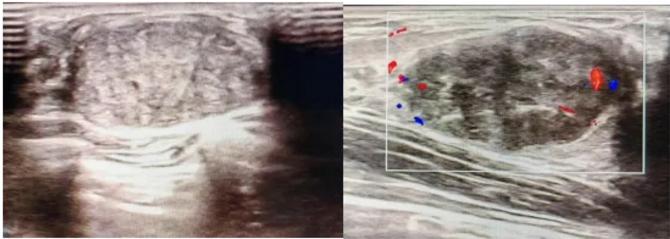

典型表現(xiàn):

橢圓形低回聲團(tuán)塊,包膜完整,內(nèi)部回聲均勻,后方回聲增強(qiáng),周邊無“蟹足樣”浸潤。

血流信號:纖維瘤血流較少,惡性常伴豐富雜亂血流。

形態(tài):良性多呈橢圓形或分葉狀,邊界光滑。

縱橫比: 良性通常<1(橫徑>縱徑) 。